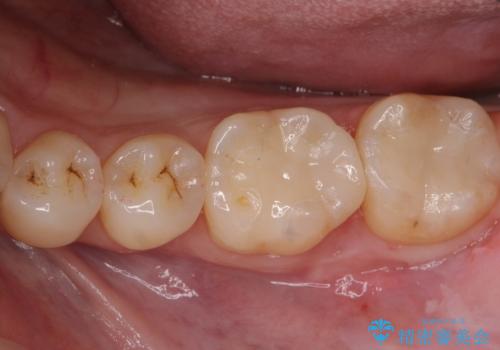

目立つ銀歯をセラミッククラウンに

【セラミッククラウン】詰め物と歯の境目に汚れが溜まる